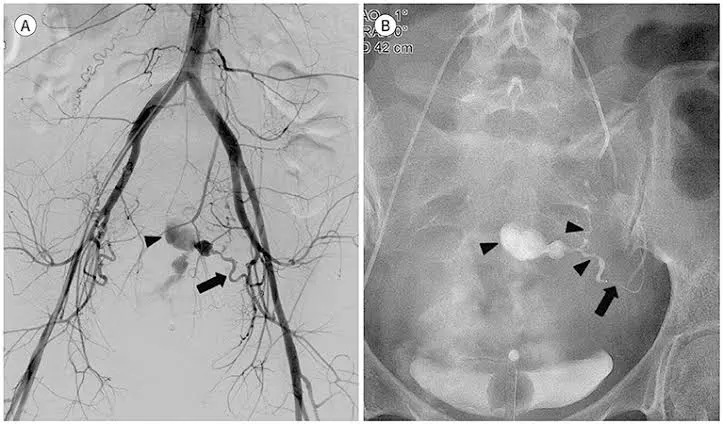

In the UAE treatment, imaging guidance is utilized to ensure the catheter passes safely through blood vessels to reach the precise area of the uterine arteries. Smaller particles are finally infused to lower blood supply for the specified areas of the uterus. Over the period, the body compensates for the foreign matter by shrinking the sizes of the fibroids or adjusting the bleeding patterns.

Uterine Arteriovenous Malformation (Uterine AVM) can be considered as a situation in which arteries as well as veins in the uterine region have a malformation or abnormal connection. The most important point about this health issue is that this malformation can lead to sudden uterine bleeding. The best treatment form in this case can be Uterine Artery Embolization.

Step 4: Embolization (Reduction of Blood Flow) Embolic particles are injected through the catheter to decrease blood flow to the selected branches of the uterine artery. This is the definitive step. For fibroids, reduced blood flow causes fibroids to shrink gradually. Reducing blood flow will assist in stopping the bleeding in cases of postpartum hemorrhage.